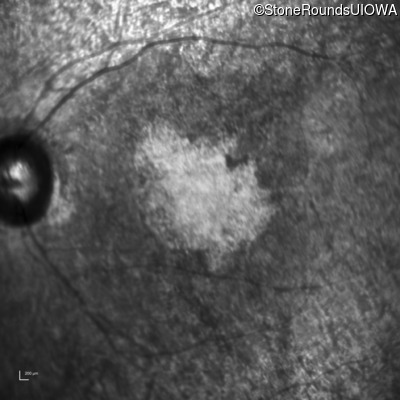

This 47 year old woman was born with a supernumerary digit on the ulnar side of both hands. As a young child, her best corrected visual acuity was completely normal. She had no difficulties with her vision until age 30 when her visual acuity could no longer be corrected to 20/20 and she began to notice some night blindness.

The clinical features supporting the diagnosis of Bardet Biedl syndrome in this patient include: bone-spicule-like pigmentation, narrowed arterioles and macular atrophy on ophthalmoscopy; photoreceptor loss on OCT; ulnar polydactyly, obesity, abnormal cognition, hypertension; and, normally sighted parents.